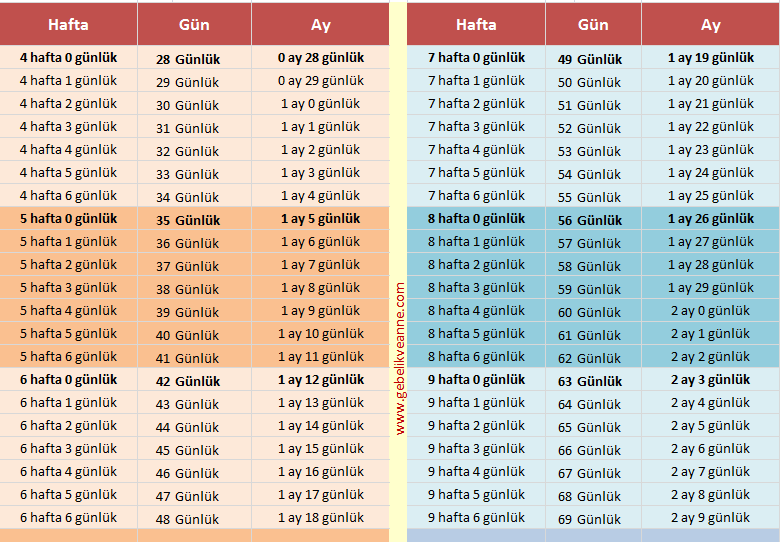

? Haftalık Gebelik ve Bebek Kaç Aylık Olur?